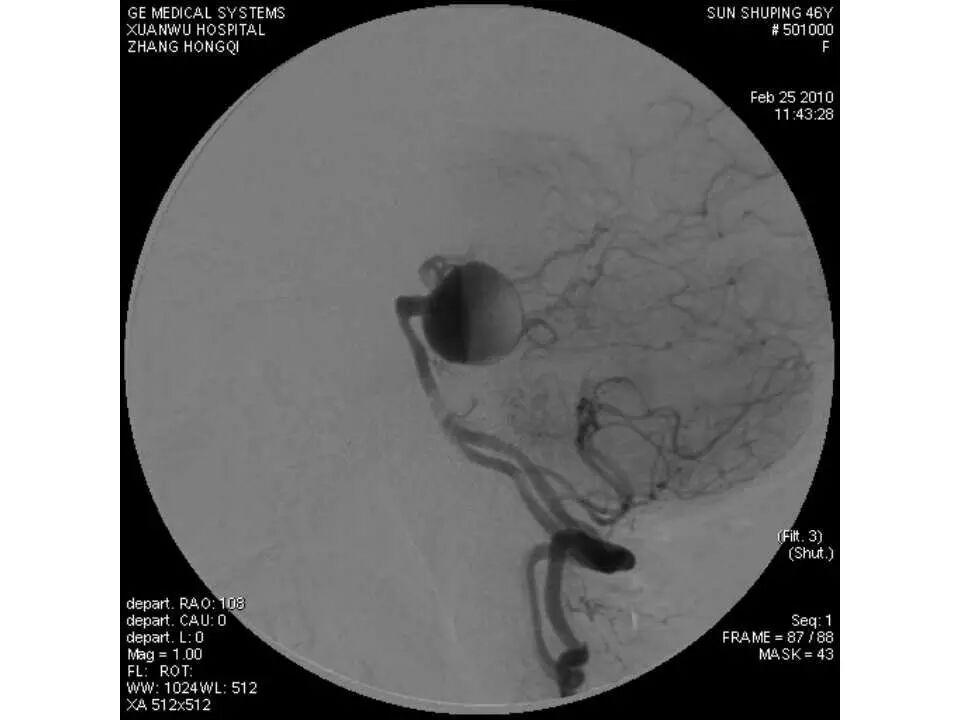

今天为大家分享的是“强生医疗CNV-神经介入专栏”第十五期,由首都医科大学宣武医院何川教授带来的“颅内动脉瘤介入治疗”精彩讲课视频及PPT,欢迎观看、阅读。文章仅代表作者个人观点,如有不同见解,欢迎同道斧正!

何川 ,首都医科大学宣武医院副主任医师,中国医师协会神经介入专业委员会常务委员,长期从事脑血管病和脊髓血管病的手术及介入治疗和相关研究工作。首都医科大学神经外科博士,师从于中国神经介入开创人凌锋教授;日本东北大学医院脑血管病治疗科博士后,师从于日本国脑血管病血管内治疗的开创者高桥教授。